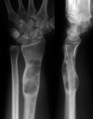

X-ray image showing enchondromas localized in the lower part of the radius of a 7-year-old girl with Ollier disease.

On radiographs, streaks of low density are seen projecting through the diaphyses into the epiphyses of the long bones, due to ectopic cartilage deposits. With age, the cartilage may calcify in the typical "snowflake" pattern.